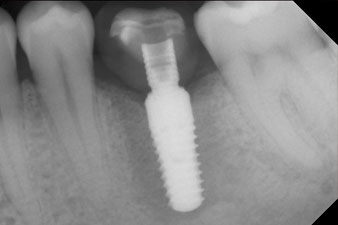

The final pictures show the screw-retained monolithic composite crown in place and the x-ray check (Fig. 9 and 10) (6).

Patients today expect quick treatment and thus determining the right time of restoration is becoming more and more important. To be able to estimate the micromovement for immediate restorations, the primary mechanically determined stability must be measured on the day of implantation. In contrast, to check that osseointegration was successful, the biologically determined secondary stability is measured. If implants are placed in soft bone, on average they tend to be more stable after uncovery than after placement (2). But if the implant is placed in hard or solid bone, as in the case study described here, the ISQ value remains constant or may even decrease if the initial values were high. The high mechanical stability is reduced by the osseointegration process and it is replaced by a biological anchorage.

The implant stability is better described as micromobility and is best measured by resonance-frequency analysis (RFA) (7, 8). Measurements are best made in two directions, as in the case study (9). The technology is optionally available as a module that can be docked to the Implantmed implantology motor. A separate device is not required. The lower value is always applicable for the therapy. Measured values are displayed on the touch screen of the implantology motor as the implant-stability quotient (ISQ). Along with the torque curve for insertion and data on preparation of the implant bed, they can be recorded on a USB stick and used for documentation for the patient and the implant. Overall, it is a very user-friendly and reliable technology for everyday work in implantology, particularly in combination with the W&H Implantmed.